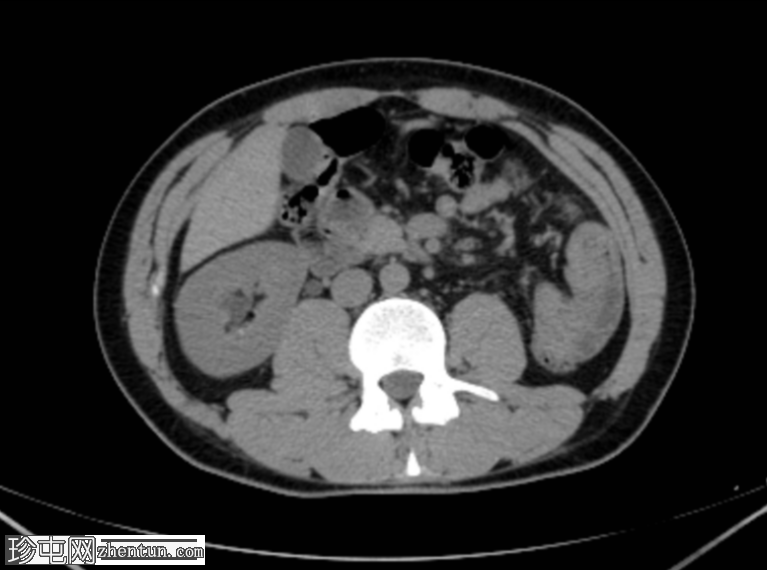

CT

轴位

平扫

左肾发育不全。

左侧精囊囊肿。

右肾代偿性肥大,右肾下盏可见微小结石。